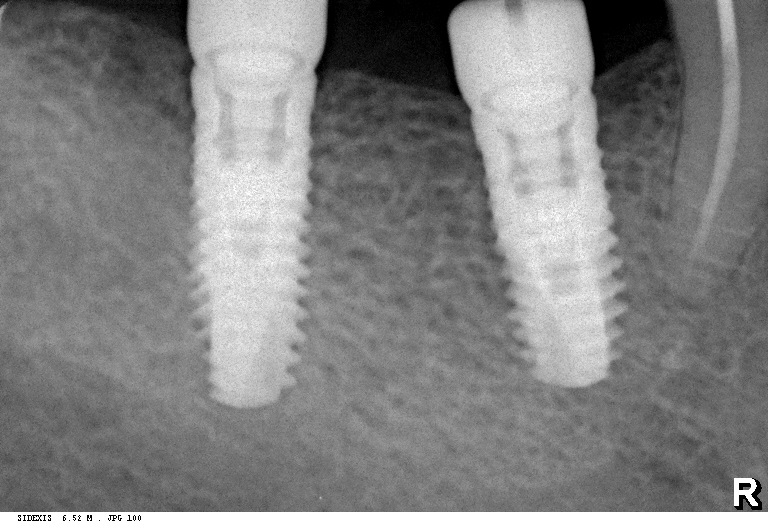

Вот пациент, ему больше пятидесяти лет. Мы удалили восьмерку и семерку, затем поставили два импланта: один в лунку седьмого зуба, а второй — на место давно отсутствующей шестерки. Снимок, сделанный сразу после имплантации (слева). Через 2,5 месяца после имплантации (справа):

На левом снимке хорошо видны края лунки зуба. На правом они, практически, незаметны. Альвеола семерки при имплантации ничем специальным не заполнялась — только кровяной сгусток и немного костной стружки, которая попала туда при подготовке лунки под имплант. И мы видим, что костная ткань великолепно регенерирует — у нее появился характерный рисунок из балок и полостей. Мы видим, что не происходит убыли костной ткани, она не проседает и никуда не уходит. Причина тому — РЕГЕНЕРАТИВНЫЕ СПОСОБНОСТИ организма.